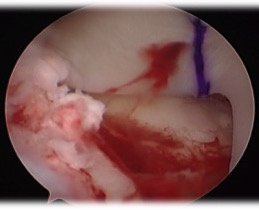

- insert guide pin, drill over, then insert box cutter

- carefully clean out with shaver